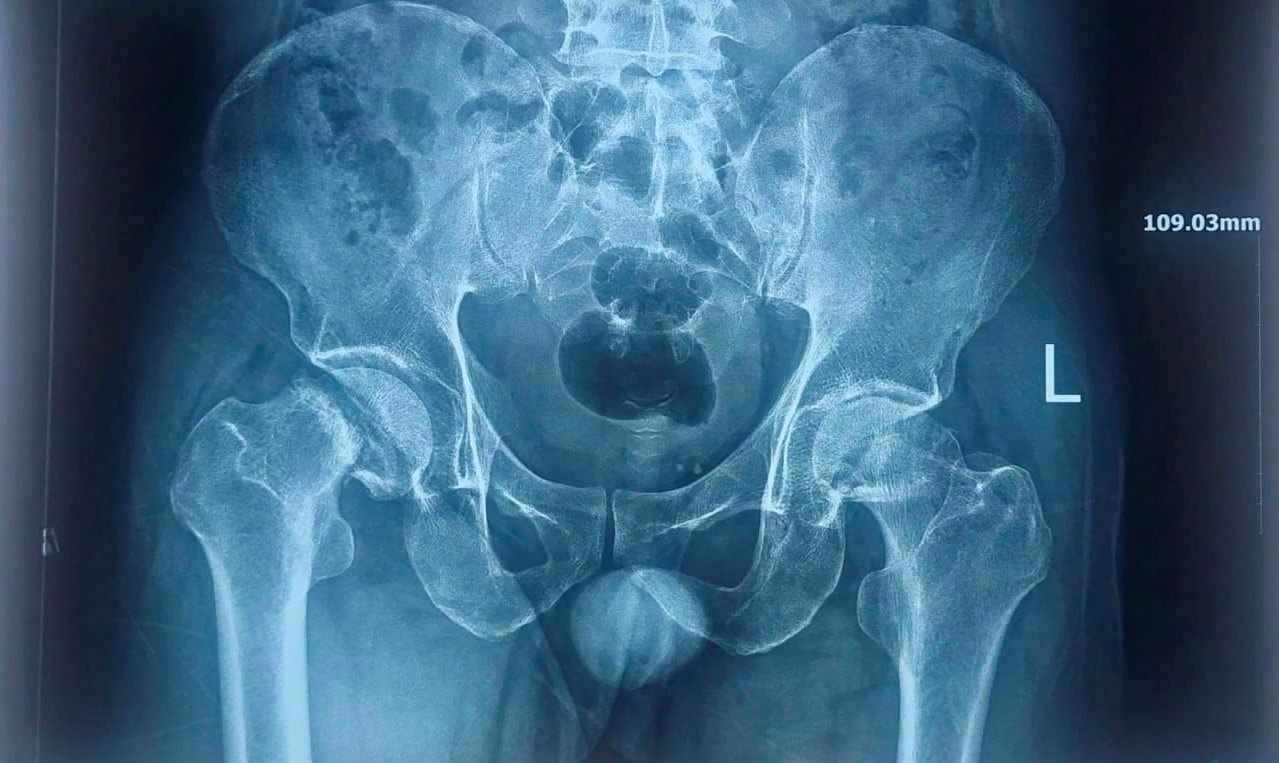

X-quang khung chậu trước khi phẫu thuật

Qua thăm khám và các xét nghiệm hình ảnh, các bác sĩ xác định bệnh nhân bị hoại tử chỏm xương đùi hai bên.

Đây là một bệnh lý nguy hiểm của khớp háng do giảm hoặc mất nguồn máu nuôi chỏm xương đùi, dẫn đến hoại tử xương, đau kéo dài và có thể gây xẹp khớp nếu không điều trị kịp thời. Bệnh nhân có chỉ định phẫu thuật.